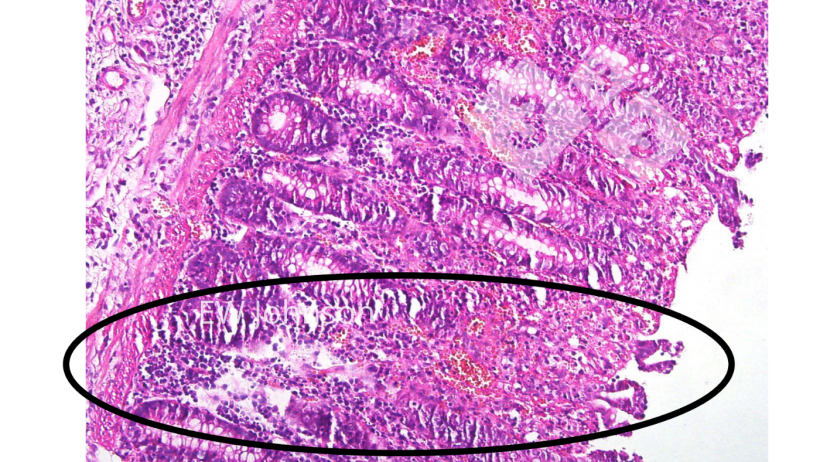

No exame histopatológico vasculite generalizada com infarto, hemorragia e trombose são observadas em múltiplos órgãos, particularmente no pulmão, baço, linfonodos, rins, cérebro e intestino. Há destruição linfóide maciça nos linfonodos e baço e vacuolização dos macrófagos alveolares. Necrose e ulceração do epitélio do cólon são frequentes (foto 4).

O uso da histopatologia para verificar lesões vacinais crônicas típicas com genes deletados pode ser muito útil. Os suínos que receberam essas vacinas de PSA muitas vezes apresentam cicatrizes crônicas ativas e lesões vasculares fibrosantes, incluindo trombos e infartos no intestino, fígado, tecidos linfóides, coração e rins. Os linfonodos podem apresentar áreas hemorrágicas, com necrose e destruição de linfócitos, e áreas com fibrose e cicatrização. Os reprodutores vacinados podem apresentar grandes áreas de necrose e fibrose pulmonar que muitas vezes são confundidas com App crônica. O vírus da vacina pode não matar o suíno, mas muitas vezes não consegue eliminar o vírus.